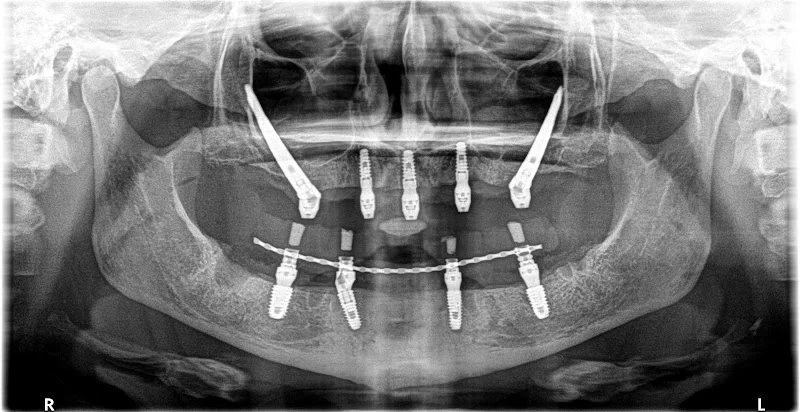

Dental implants provider